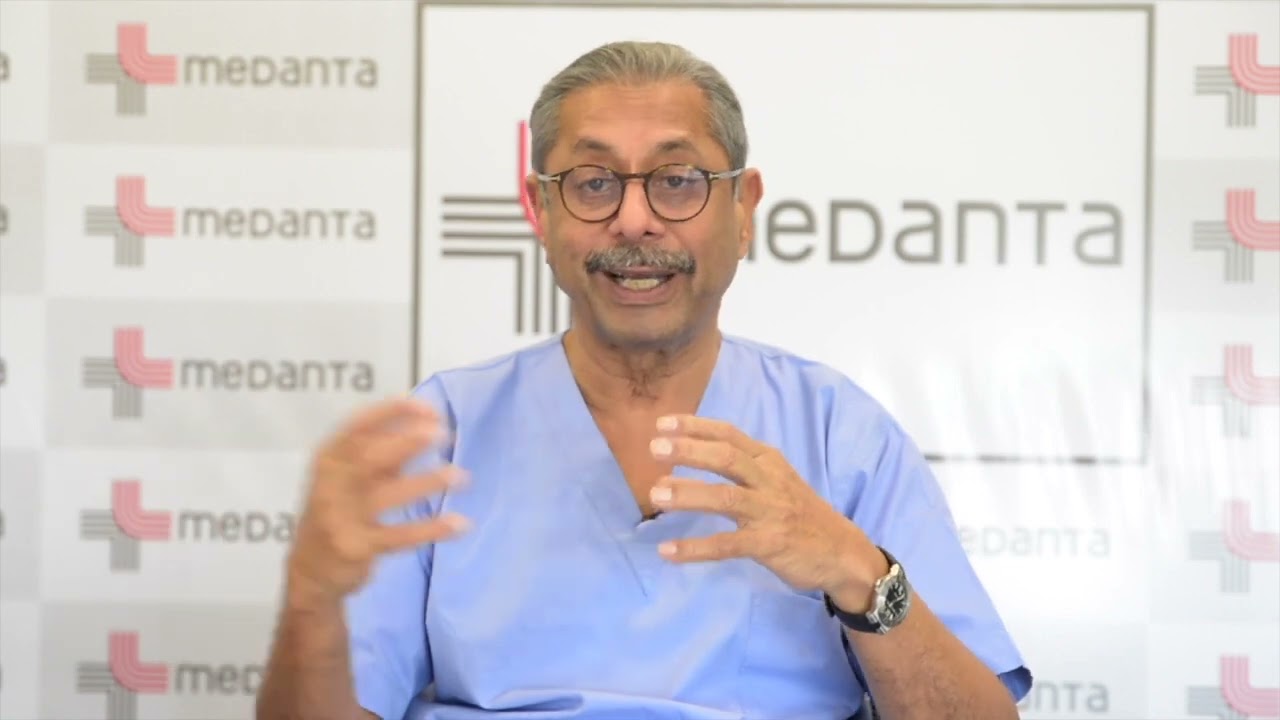

Jaipur Saturday Session 1 Bladder Surgery

Humans of Robotic Surgery, KS Awards, Robotics, Surgeon, Video Library ';